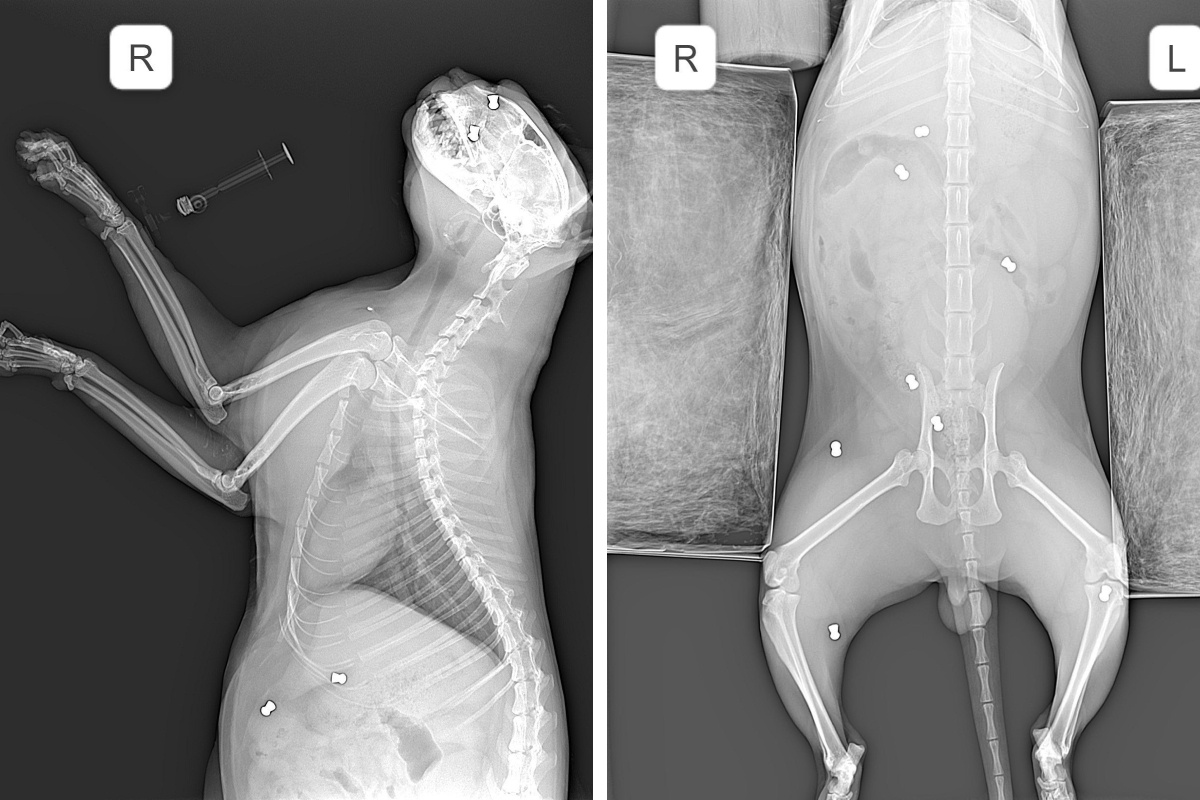

Питомца сразу отвезли в ветклинику, где его обследовали и сделали рентген. Судя по снимку, в теле и голове животного около девяти пуль. Некоторые из них, например около глаза, видны даже без рентгена.

Подруга хозяйки Ирина рассказала нам, что сегодня ветеринары смогут дать прогноз по состоянию кота. Медикам удалось извлечь поверхностные пули, по более глубоким поражениям ситуация прояснится позже. Также пока неизвестно, удастся ли спасти глаз животного.